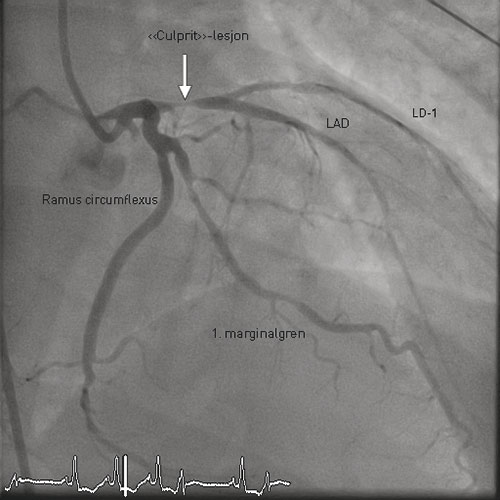

On arrival at the university hospital, the patient was taken immediately to the angiography laboratory. A coronary angiogram showed three-vessel disease with stenosis proximally in the anterior descending branch of the left coronary artery (LAD), stenosis in a marginal branch of the circumflex branch and several stenoses in the right coronary artery (Fig. 1). The LAD stenosis was considered to be the culprit lesion, and PCI was performed with implantation of a conventional metal stent – with a favourable angiographic result.

Figure 1  Coronary angiogram showing the left coronary artery. The culprit lesion proximally in the left anterior descending…

Figure 1 Coronary angiogram showing the left coronary artery. The culprit lesion proximally in the left anterior descending artery, LAD, is marked with an arrow. LD-1 = first diagonal branch